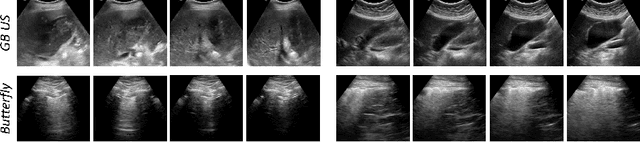

Abstract:Rich temporal information and variations in viewpoints make video data an attractive choice for learning image representations using unsupervised contrastive learning (UCL) techniques. State-of-the-art (SOTA) contrastive learning techniques consider frames within a video as positives in the embedding space, whereas the frames from other videos are considered negatives. We observe that unlike multiple views of an object in natural scene videos, an Ultrasound (US) video captures different 2D slices of an organ. Hence, there is almost no similarity between the temporally distant frames of even the same US video. In this paper we propose to instead utilize such frames as hard negatives. We advocate mining both intra-video and cross-video negatives in a hardness-sensitive negative mining curriculum in a UCL framework to learn rich image representations. We deploy our framework to learn the representations of Gallbladder (GB) malignancy from US videos. We also construct the first large-scale US video dataset containing 64 videos and 15,800 frames for learning GB representations. We show that the standard ResNet50 backbone trained with our framework improves the accuracy of models pretrained with SOTA UCL techniques as well as supervised pretrained models on ImageNet for the GB malignancy detection task by 2-6%. We further validate the generalizability of our method on a publicly available lung US image dataset of COVID-19 pathologies and show an improvement of 1.5% compared to SOTA. Source code, dataset, and models are available at https://gbc-iitd.github.io/usucl.